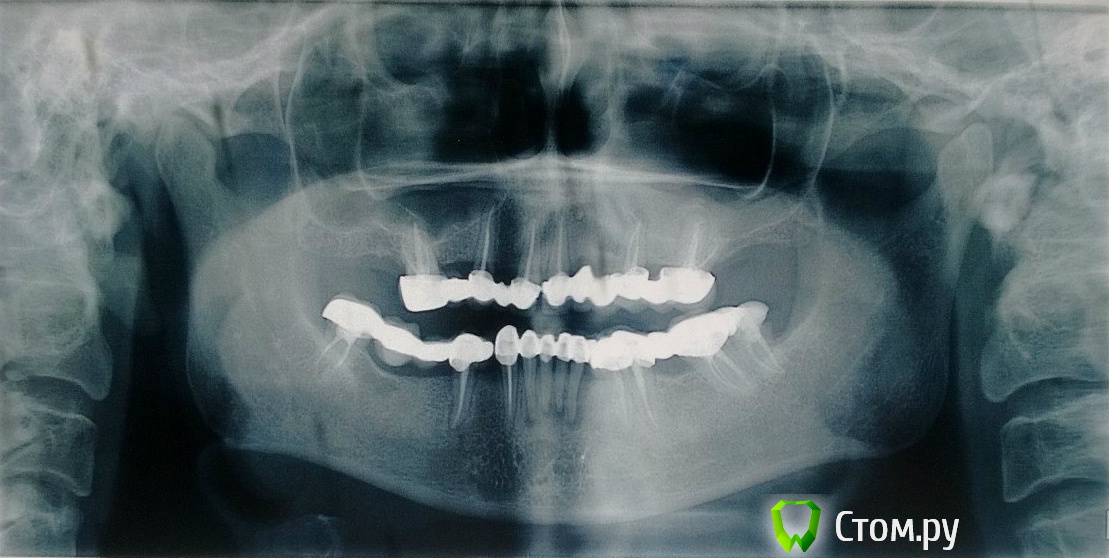

НастяЦЦЦ Опубликовано 22 марта, 2014 Поделиться Опубликовано 22 марта, 2014 Здравствуйте, уважаемые стоматологи! Буду очень благодарна за консультацию.У меня все верхние зубы (их осталось шесть) - под коронкой. Сначала это был один цельный мост, потом он раскололся напополам, половинки то и дело слетают, надо что-то делать.Стоматолог, которому я решила довериться, посмотрев снимок, предлагает: удалить ВСЕ шесть зубов наверху, поставить временно съемный протез, через полгода - поставить шесть имплантов, на них - новую коронку.Из шести моих зубов, по мнению врача, только два в центре можно было бы оставить (сохраниение остальных чревато тяжелым гайморитом и еще какими-то страшными проблемами), но эти два центральных, по его словам, "погоды не делают" - проще и логичней удалить их тоже.Мне очень страшно разом удалить все мои оставшиеся зубы, поэтому решила узнать мнения других врачей. Пока по устным консультациям расклад 2:1 в пользу описанного решения, один врач из трех сказал, что гайморит - ерунда ("у вас и так гайморит"))), и что он берется сделать мне новую коронку, укрепив мои зубы, и обещает, что лет 10 она у меня простоит.Что скажете вы?Еще раз заранее спасибо за ответы, они очень важны для меня! Ссылка на комментарий

Гарриевич Опубликовано 29 марта, 2014 Поделиться Опубликовано 29 марта, 2014 Чтобы тема выделялась жирным шрифтом, нужны новые ответы, которые Вы еще не виделиА по теме, на этом снимке видно что проблемы есть, план должен быть такой: снимаем конструкции, оцениваем здоровье каждого отдельного зуба и исходя из этого принимаем решение. Удалять исходя из принципа "до кучи" не стоит, если речь идет об имплантации, то свои зубы можно не связывать мостами и тогда они прослужат дольше 2 Ссылка на комментарий

pawa Опубликовано 29 марта, 2014 Поделиться Опубликовано 29 марта, 2014 скорее всего, раз коронки неоднократно слетали, то зубы под ними могли разрушиться и... надо, конечно , во рту смотреть, одного панорамного снимка недостаточно. +1 к имплантации 1 Ссылка на комментарий